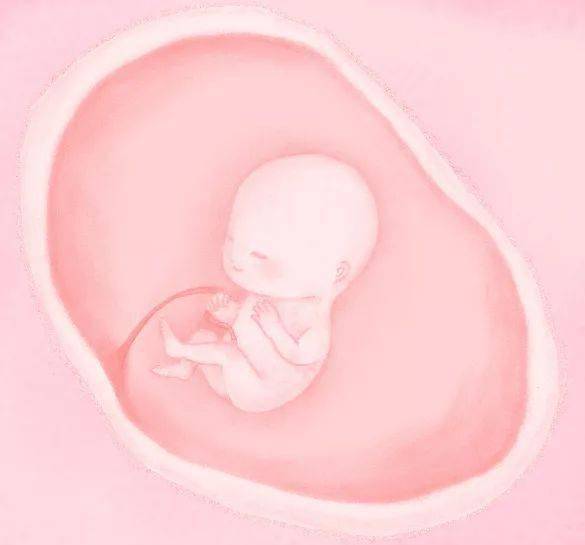

▲ 孕 2 月

眼睛、唇开始生出,心脏开始构建, 神经管开始连接大脑和脊髓,逐渐长出肢体,长耳朵,外生殖器可辨认,牙齿开始发育,可以称为胎儿了,B超可见到胎心管搏动。